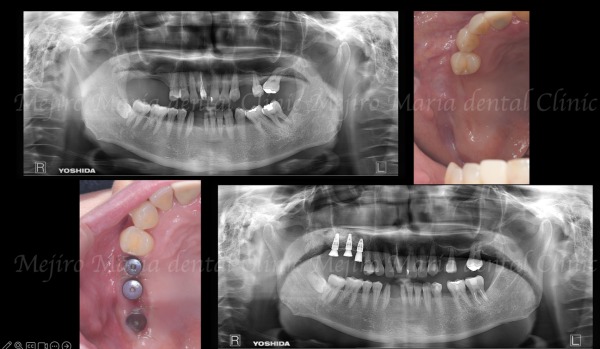

当院が大切にしているのは、できるだけ安心して治療を受けていただくこと、そして結果を実感していただくことです。そのために、院内の衛生管理体制やバリアフリー設計など環境面にもこだわり、患者様ができるだけ不安やストレスを感じないよう配慮。そして、マイクロスコープや歯科用CTなどの先端医療機器を活用し、精密根管治療を得意とする院長や大学病院から招いた歯科医師でチームを組んで、専門性の高い治療をご提供しています。